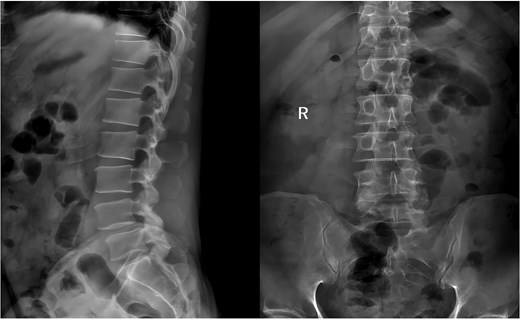

Following the surgery, the patient remained in stable condition with no reported discomfort. Postoperative radiographs verified complete extraction of the guidewire, with no residual fragments observed at the fracture site (Fig. 6). The patient experienced an uneventful recovery, and subsequent follow-up evaluations demonstrated satisfactory outcomes.

Postoperative anteroposterior and lateral radiographs of the lumbar spine.